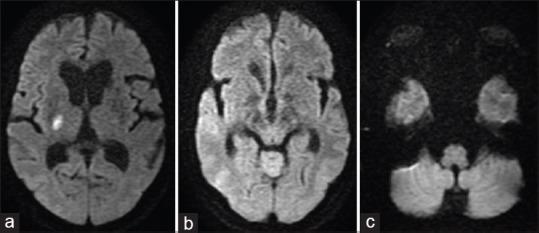

Infarcts involving the thalamus can yield many deficits, including sensory syndromes, altered consciousness, and cognitive disturbances, depending on the thalamic vascular territory involved. Isolated truncal contrapulsion due to pure thalamic infarct has been rarely reported. Truncal lateropulsion is a compelling sensation of being pulled toward one side that cannot be explained by weakness or limb ataxia. It is commonly reported in lateral medullary infarcts. It may occur with lesions that involve the peripheral vestibular system, brainstem, cerebellum, basal ganglia, ponto-mesencephalic, and thalamic lesions. We hereby report a 64-year-old woman who presented with truncal contrapulsion as the sole manifestation of an acute right lateral thalamic infarct.

根据所累及的丘脑血管区域,累及丘脑的梗死可导致多种功能缺损,包括感觉综合征、意识改变和认知障碍。因单纯丘脑梗死导致的孤立性躯干对侧推挤很少见报道。躯干侧方推挤是一种被拉向一侧的强烈感觉,无法用无力或肢体共济失调来解释。它常见于延髓外侧梗死。它可能与累及外周前庭系统、脑干、小脑、基底神经节、脑桥中脑以及丘脑的病变有关。我们在此报告一名64岁女性,其以躯干对侧推挤作为急性右侧丘脑梗死的唯一表现。